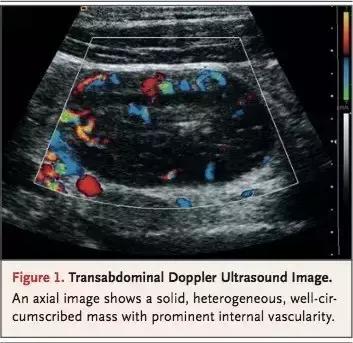

B超可见右髂总动脉前有一异质边界清晰的包块,包块内有血管。*丸睾**和阴囊正常。